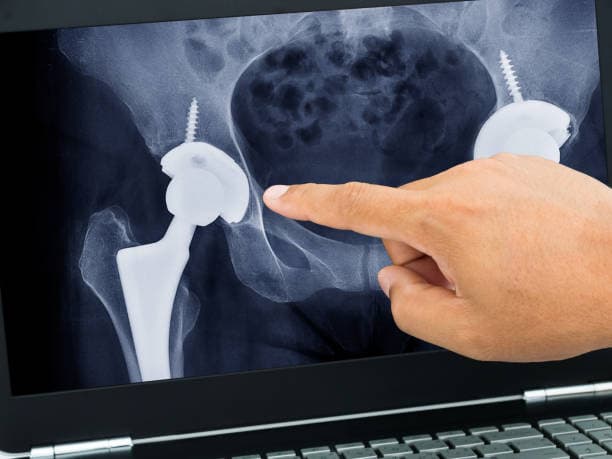

There are different types of hip arthroplasty, including total hip replacement, where both the femoral head and the acetabulum are replaced, and partial hip replacement, which involves only the femoral head. The choice of procedure depends on factors such as the patient's age, activity level, and the extent of joint damage. Minimally invasive techniques are also available, which involve smaller incisions and aim to reduce recovery time and postoperative discomfort.

Total hip arthroplasty (THA) is the most common and widely performed hip replacement procedure. It involves replacing both the acetabulum (hip socket) and the femoral head (the ball) with prosthetic components made of metal, ceramic, or plastic. This procedure is typically recommended for patients with severe osteoarthritis, rheumatoid arthritis, or significant hip fractures that impair mobility and cause chronic pain. THA aims to relieve pain, improve joint function, and enhance the patient's quality of life. The prosthetic components are designed to mimic the natural movement of the hip joint, allowing for smooth and pain-free motion.

Hip hemiarthroplasty involves replacing only one part of the hip joint, typically the femoral head, while leaving the acetabulum intact. This procedure is often performed for patients with specific hip fractures or conditions that do not affect the acetabulum. Hemiarthroplasty is generally less invasive than total hip replacement and can be a good option for elderly patients or those with lower activity levels. It provides pain relief and improved function, but may not offer the same long-term durability as total hip replacement.